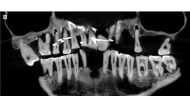

French aristocrat's golden dental secret revealed 400 years on 26 Jan 2023 - 05:58 pm

A handout picture released by the French National Institute of Archaeological Researchs (Inrap) on January 25, 2023 shows a close up in picture and in radiograph of the skull of Anne d'Alegre, a 17th-century aristocrat. (Photo by Handout / INRAP / AFP)